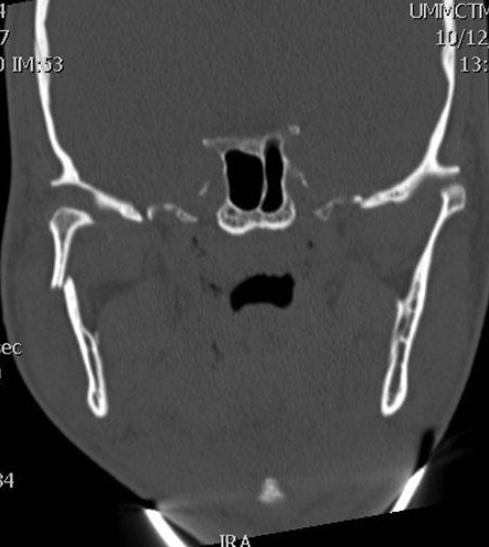

A 27-year-old man is admitted to the emergency department after being injured in an altercation. Physical examination shows objective malocclusion with a left-sided crossbite and right-sided open bite. A CT scan is shown. Which of the following muscles is most likely responsible for these radiographic and physical examination findings?

The correct response is Option B.

The patient described has typical radiographic and physical exam findings of a right subcondylar mandibular fracture. Anteromedial displacement of the condylar segment out of the glenoid fossa occurs secondary to pull from the lateral pterygoid muscle, which normally functions in anterior translation of the condyle across the articular eminence of the temporal bone during wide mouth opening. This leads to loss of height of the mandibular ramus and a premature occlusion on the fracture side. This causes the typical findings of condylar/subcondylar fractures: ipsilateral crossbite and contralateral open bite. The masseter and medial pterygoid form the pterygomasseteric sling, which attaches from the skull base and zygoma to the inferior mandibular border, and is responsible for fracture displacement after angle and body fractures. The mylohyoid and genioglossus muscles run along the floor of the mouth and can contribute to fracture displacement in the body and parasymphyseal region.